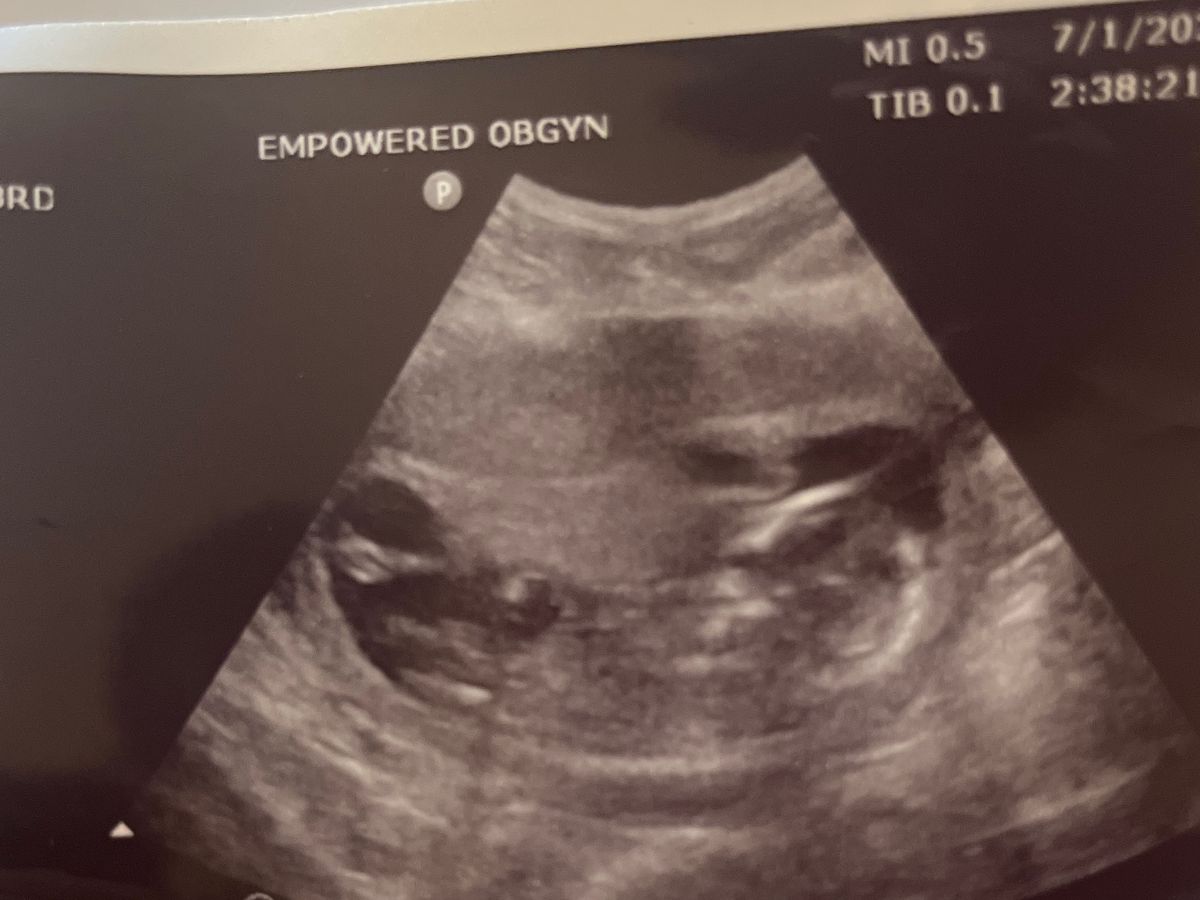

On Friday, July 12, 2024, during our 19 week prenatal visit at our OB/GYN, a heartbeat was not found with the doppler and our OB wanted an ultrasound to try to get the heartbeat. This didn’t alarm us initially as this has happened during nearly every prenatal visit.

This ultrasound wasn’t like the others. No heartbeat. No activity. At first, as the ultrasound tech kept working, I said aloud “something doesn’t seem right. I’m nervous.” She tried to calm me, but as my OB came in and took my hand, and said “There’s no heartbeat. Her heartbeat has stopped” I could no more than blink the tears away and try to hold myself together. Our daughter, the child that we looked so forward to meeting and being her parents and loving her….was never going to go home with us.